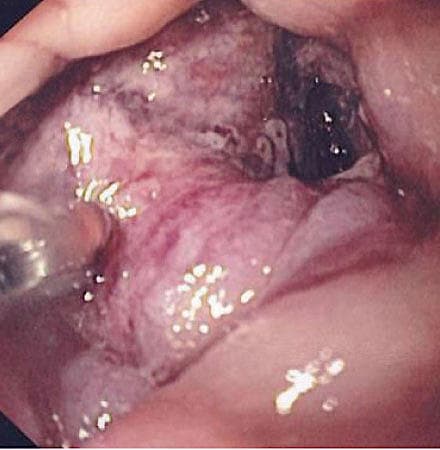

overvågningen, hvor man ved sprayapplikation af farvestof på mucosa fremhæver strukturelle forandringer, såsom dysplasier. I et case-kontrol-studie fra 2004 fandt man ved kromoendoskopi dysplasi i syv ud af 157 målrettede biopsier mod ingen ud af 2.904 randomiserede kvadrantbiopsier, der var udført efter WHO’s anvisninger [26].